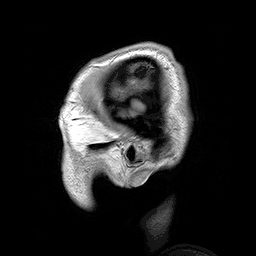

![]() Plano sagital o parasagital de una RM de la cabeza de un paciente con una macrocefalia benigna antes de una conmoción cerebral. | ||